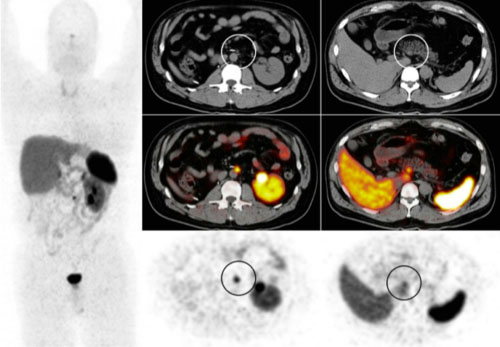

DOTA-TOC PET/CT in patient after resection of ileal primary, demonstrating focal uptake along the aorta (middle column) consistent with small residual disease. Right column demonstrates physiologic uptake in the uncinate process.